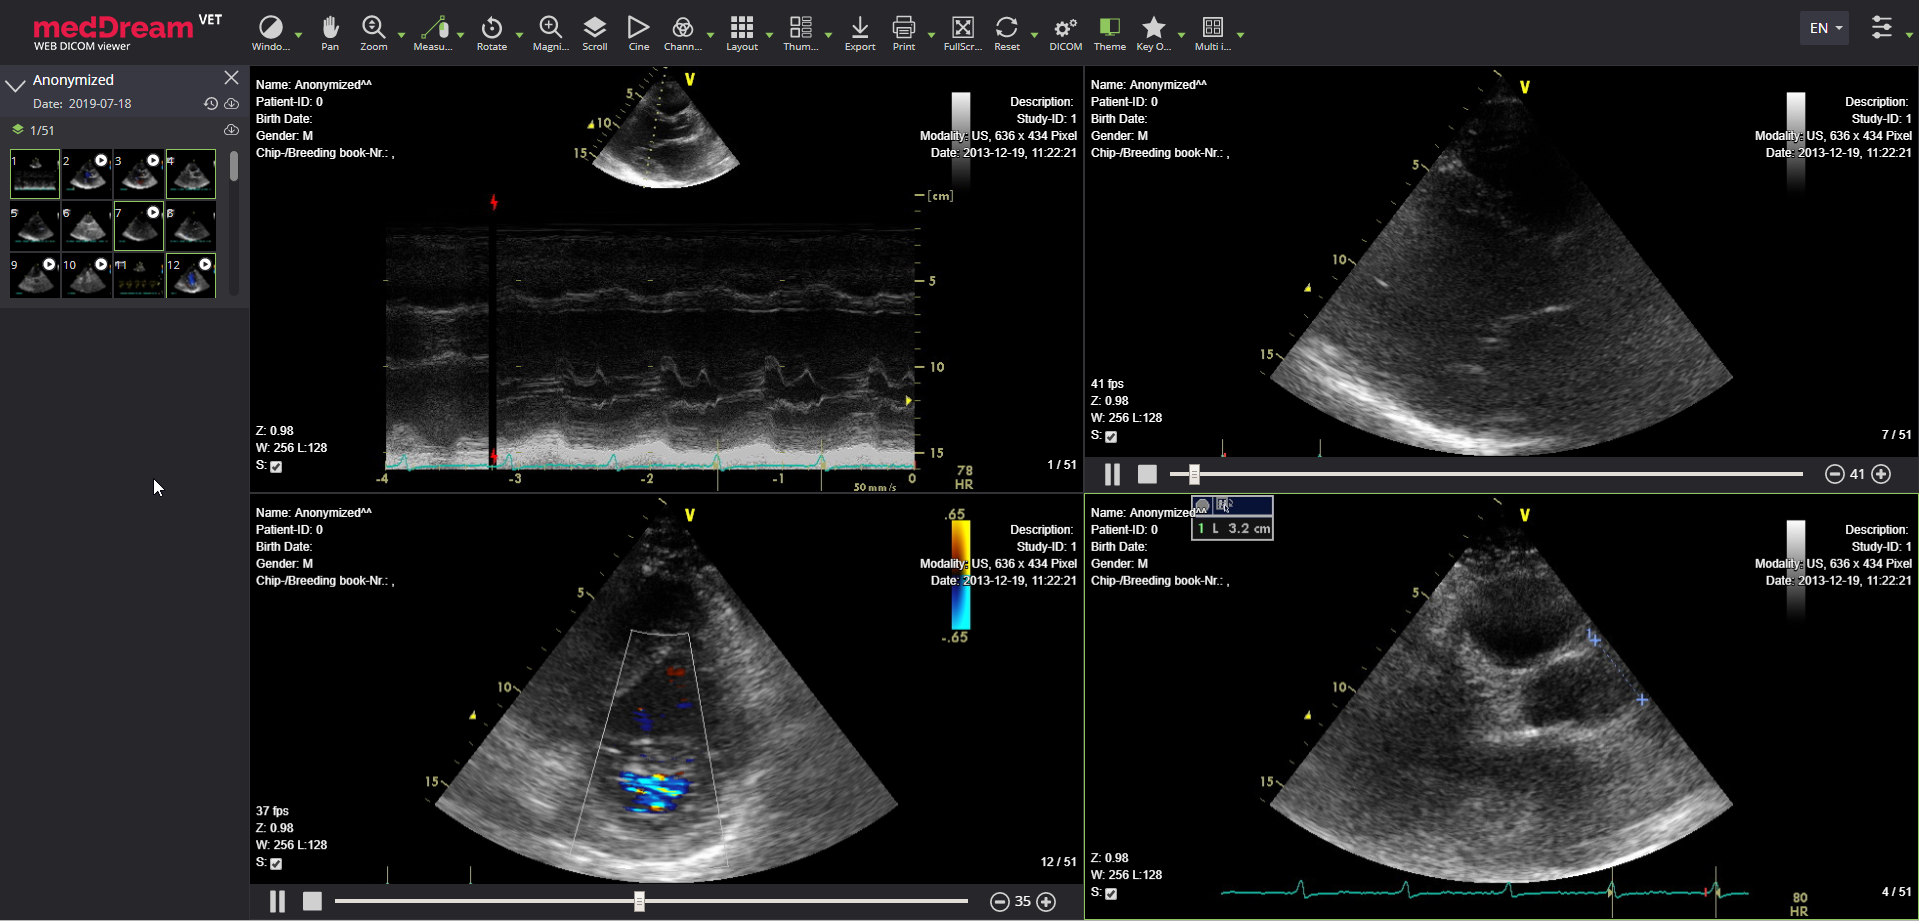

meddream vet dicom viewer es us video

MedDream VET DICOM Viewer's main features:

• Simultaneous playback of up - to 9 DICOM video files;

• Comfortable bar of series preview with thumbnails;

• DICOM ECG supported (read more about VET ECG & Ultrasound);